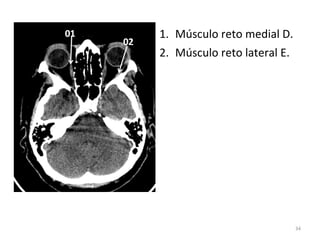

1. Músculo reto medial D.

2. Músculo reto lateral E.